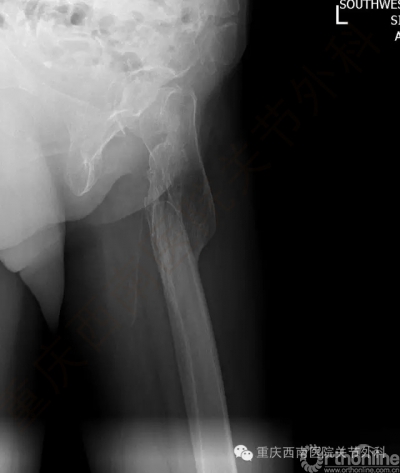

1996年的车祸导致她左侧股骨骨折形成严重的畸形愈合,股骨前后错开,髓腔封闭,类似“双截棍”,脊柱固定侧弯(图3)。

如果按照传统的手术方法需要首先截断股骨重新复位,然后劈开髓腔封闭处放入以放入人工股骨柄,最后使用钢缆捆绑固定。其结果变成为了治疗一个部位的骨折,必须医源性造成其他两个部位的额外骨折,手术创伤大风险高,术后需要卧床3个月到半年,并发症尤其是感染的发病率高。

如果她能使用上个体化截骨导航器,就能精准判断出畸形髓腔的中心点,从而绕开硬化封闭的髓腔,使用常规髋关节置换手术技术即可完成手术,避免了广泛的切开,额外的截骨,大大减少手术创伤,手术安全准确,康复更加迅速。抱着这一希望,2016年5月13日她来到西南医院关节外科。5月14日接受下肢CT三维重建扫描后,关节外科范华全工程师在杨柳教授的指导下准确迅速的完成了截骨导航器设计(图4)。